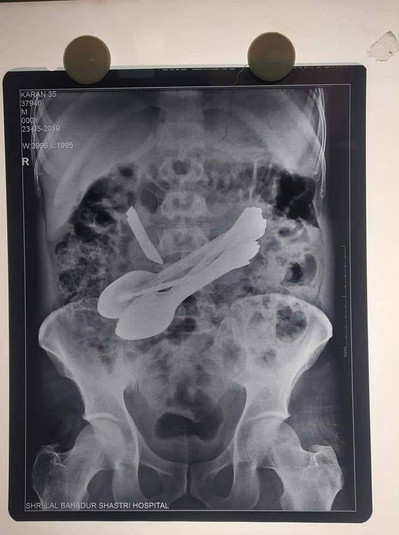

К индийским медикам обратился мужчина с болями в животе, он был доставлен в правительственный медицинский колледж Лал Бахадур Шастри в районе Манди, Индия, где врачи сделали рентген и четко обнаружили столовые приборы внутри кишечника пациента и решили оперировать.

Во время процедуры врачи удалили семь маленьких стальных ложечек, две зубные щетки, две маленькие отвертки, маленький нож и стержень.